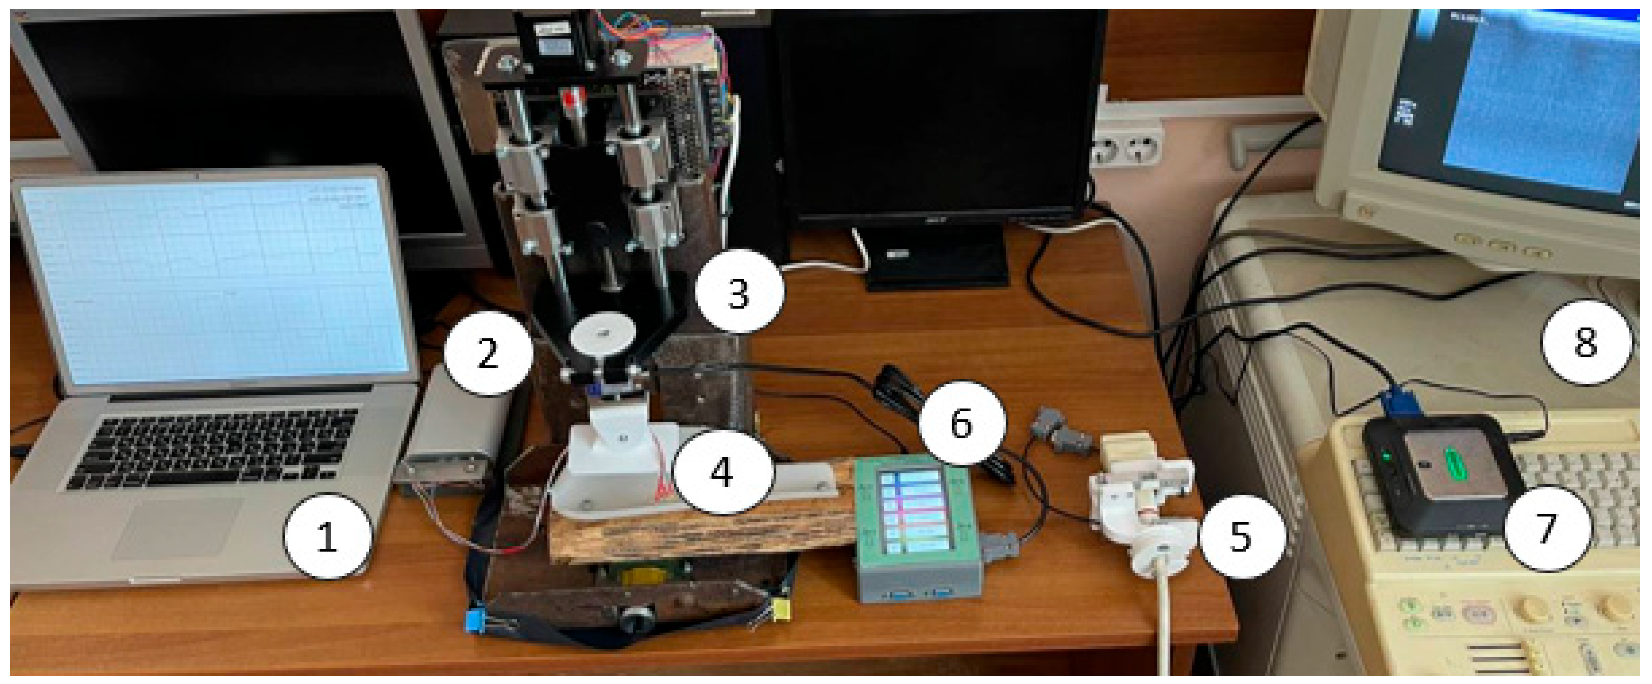

2.5. Laboratory Facilities Diagram